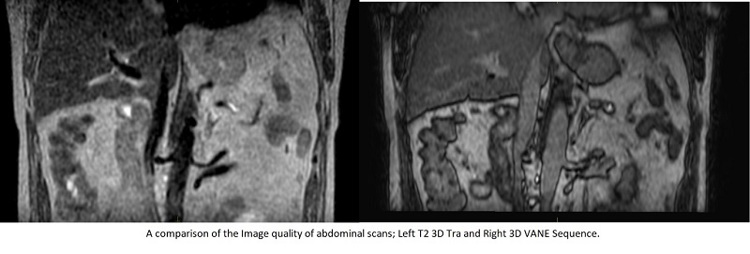

The innovation of the Phillips 3D VANE sequence, which reduces motion artefact when patients are breathing normally, and the imminent introduction of comprehensive motion management (CMM) will also support this initiative. You can read further information on the use of CMM on the Elekta website.